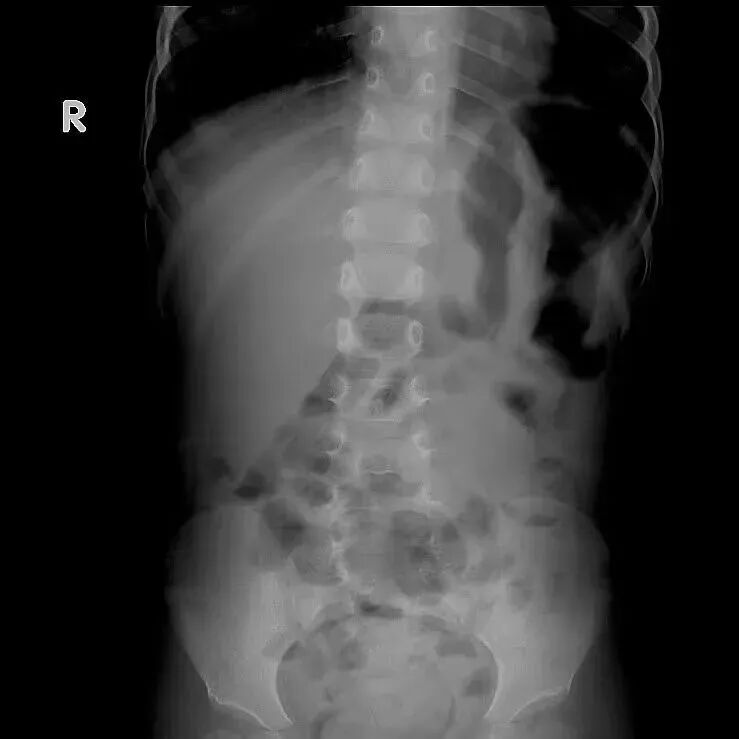

春节期间,儿科收治多例肠梗阻的患儿,究其原因,多为肠道病毒感染及不良饮食结构导致,其中6岁的小明因春节期间进食较多的零食、饮料及油炸食品等出现频繁呕吐,伴有腹痛来诊,确诊肠梗阻,与家长沟通后立即收住院治疗,给予灌肠通便,暂禁食、同时补液维持内环境稳定等,经过一系列治疗,小明的病情得到了有效缓解并逐渐恢复正常饮食和生活。

小儿肠梗阻顾名思义就是指肠管内、外的病变引起肠内容物的正常运行受阻,是小儿外科常见的急腹症,发病率在2%-5%,临床表现主要有:腹痛、呕吐、腹胀和停止排便排气;严重的肠梗阻会导致肠坏死、肠穿孔,甚至危及生命。